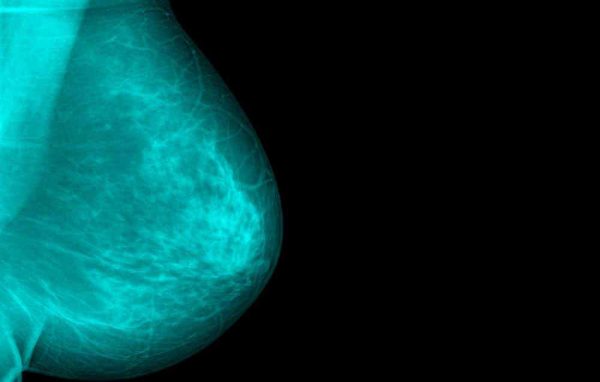

Shumë gra të diagnostikuara me kancer të gjirit ndajnë një përjetim të përbashkët: Ato kanë ndierë një gjëndër, e cila rezultoi të ishte kanceroze.

Por, gjëndra nuk është simptoma e vetme e kancerit të gjirit. Një studim i prezantuar nga Instituti Kombëtar për Hulumtimin e Kancerit, në Britani, tregoi se 1 në 6 femra të diagnostikuara me kancer të gjirit kishin ndierë fillimisht simptoma të ndryshme nga gjëndra. Duke qenë se shumë pak femra kanë ifnromacione në lidhje me këto simptoma të hershme të kancerit të gjirit, përfundojnë duke u diagnostikuar në fazat e fundit të sëmundjes.

Ja cilat janë disa nga simptomat e para të kancerit të gjirit për të cilat mund të mos keni dëgjuar më parë: